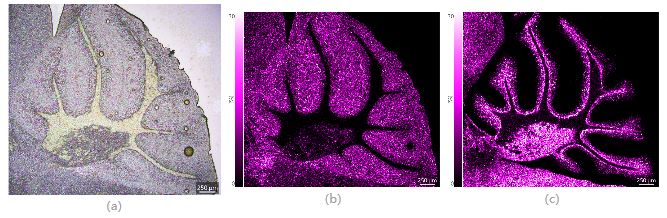

圖3 小鼠腦切片(整體)光學(xué)圖像及質(zhì)譜圖像 (a) 光學(xué)圖像;(b) PI(38:4)的質(zhì)譜圖像;(c) Sulfatide (C24:1)的質(zhì)譜圖像,空間分辨率15μm

根據(jù)檢測(cè)區(qū)域的大小及檢測(cè)目標(biāo),可選擇顯微鏡的不同放大倍數(shù)拍攝微小部位更加清晰的光學(xué)圖像并進(jìn)行高空間分辨率的成像質(zhì)譜分析。通過(guò)質(zhì)譜圖像與光學(xué)圖像的準(zhǔn)確疊加,判斷化合物的真實(shí)分布位置。對(duì)小鼠小腦區(qū)域進(jìn)行空間分辨率為5μm的高空間分辨率檢測(cè),采集區(qū)域包括662x595, 共393,890像素點(diǎn),檢測(cè)時(shí)間約為2.2小時(shí)。

圖4 小鼠腦切片(局部:小腦)光學(xué)圖像及質(zhì)譜圖像 (a) 光學(xué)圖像;(b) PI(38:4)的質(zhì)譜圖像;(c) Sulfatide (C24:1)的質(zhì)譜圖像,空間分辨率5μm